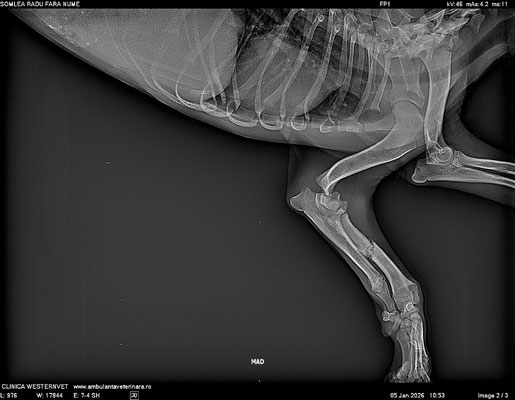

Die folgenden Tage waren geprägt von Tierarztbesuchen, Bluttests und Röntgenaufnahmen. Drei Frakturen und eine schwere Anämie machten große Sorgen, doch es gab auch gute Nachrichten: keine lebensbedrohlichen Erkrankungen. Schon nach wenigen Tagen zeigte sie kleine, aber wichtige Fortschritte – sie fraß besser, wedelte vorsichtig mit dem Schwanz, begrüßte ihre Menschen und versuchte ihnen zu folgen.

The following days were filled with vet visits, blood tests, and X-rays. Three fractures and severe anemia caused great concern, but there was also good news: no life-threatening conditions. After just a few days, she showed small but important improvements—she ate better, wagged her tail cautiously, greeted her people, and tried to follow them.